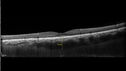

Advanced age-related macular degenerationvu 251 fois87 year old female. Severe macular bleed 15 years ago OD. Now with disciform scar. Left eye has progressing geographic atrophy.

VA OD: HM, OS: 5/200. IOP normal OU17 Mars 2024